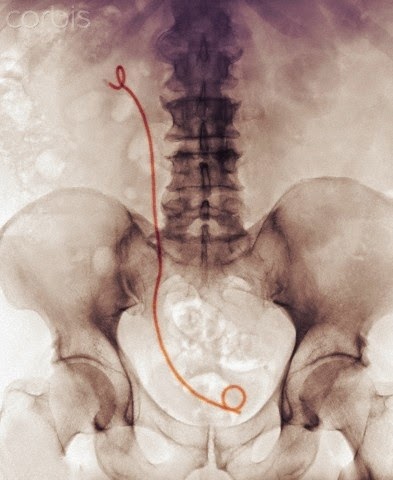

Tres imagenes de rayos X de portadores de catéteres doble J

La primera y la segunda son coloreadas; la tercera es de un doble portador.

Las dos últimas son de SciencePhotoLibrary.